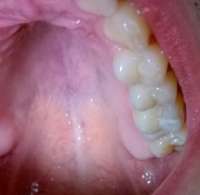

14734399434650.jpg (61Кб, 960x720)

14734399434661.jpg (64Кб, 960x720)

>>514662

Грамотный терапевт с микроскопом тебе нужен. На крайняк - апикальная хирургия.

пики из паблика, который чекаю. Кейс одного из докторов. Мб что-то поймешь. Сравни со своей НЕХ и вот что с ней можно сделать

Ты кажется стрелку не на тот зуб показал на своём пике. У тебя там зуб без пломбы даже. кек.

Мосты - хуйня. Избегай их. Только имплант если уж решишь удалять